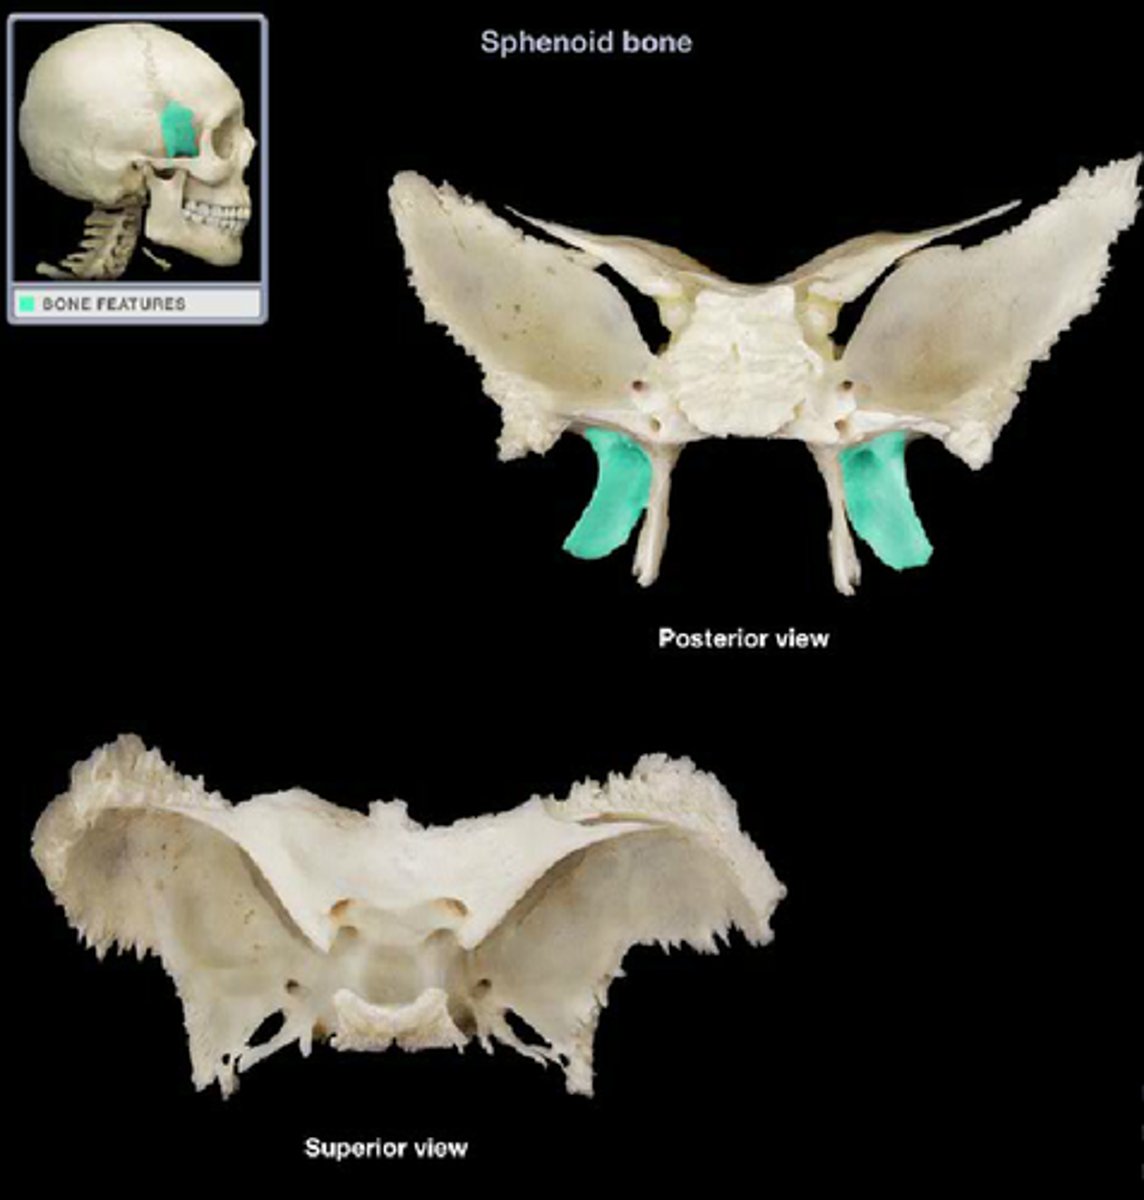

sphenoid bone

lesser wings

greater wings

pterygoid processes

sella turcica

tuberculum sellae

dorsum sellae

posterior clinoid processes

optic foramen